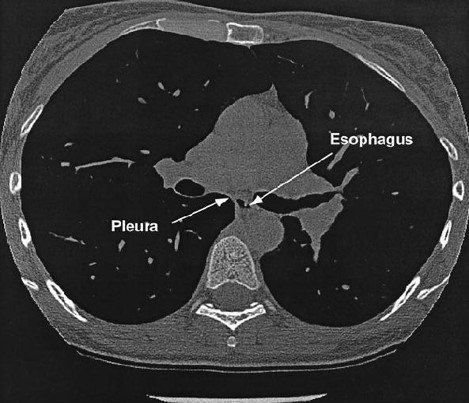

La Ppl può essere misurata direttamente solo inserendo un catetere nello spazio pleurico, operazione non facilmente realizzabile nella pratica clinica. Fortunatamente, la pressione nel terzo tratto inferiore dell’esofago(PES) è simile alla pressione all’interno dell’adiacente pleura [6]. Ciò risulta evidente nella Figura 1, che mostra una sezione TC trasversale del torace dove si può vedere chiaramente la stretta vicinanza dell’esofago allo spazio pleurico.

Figura 1